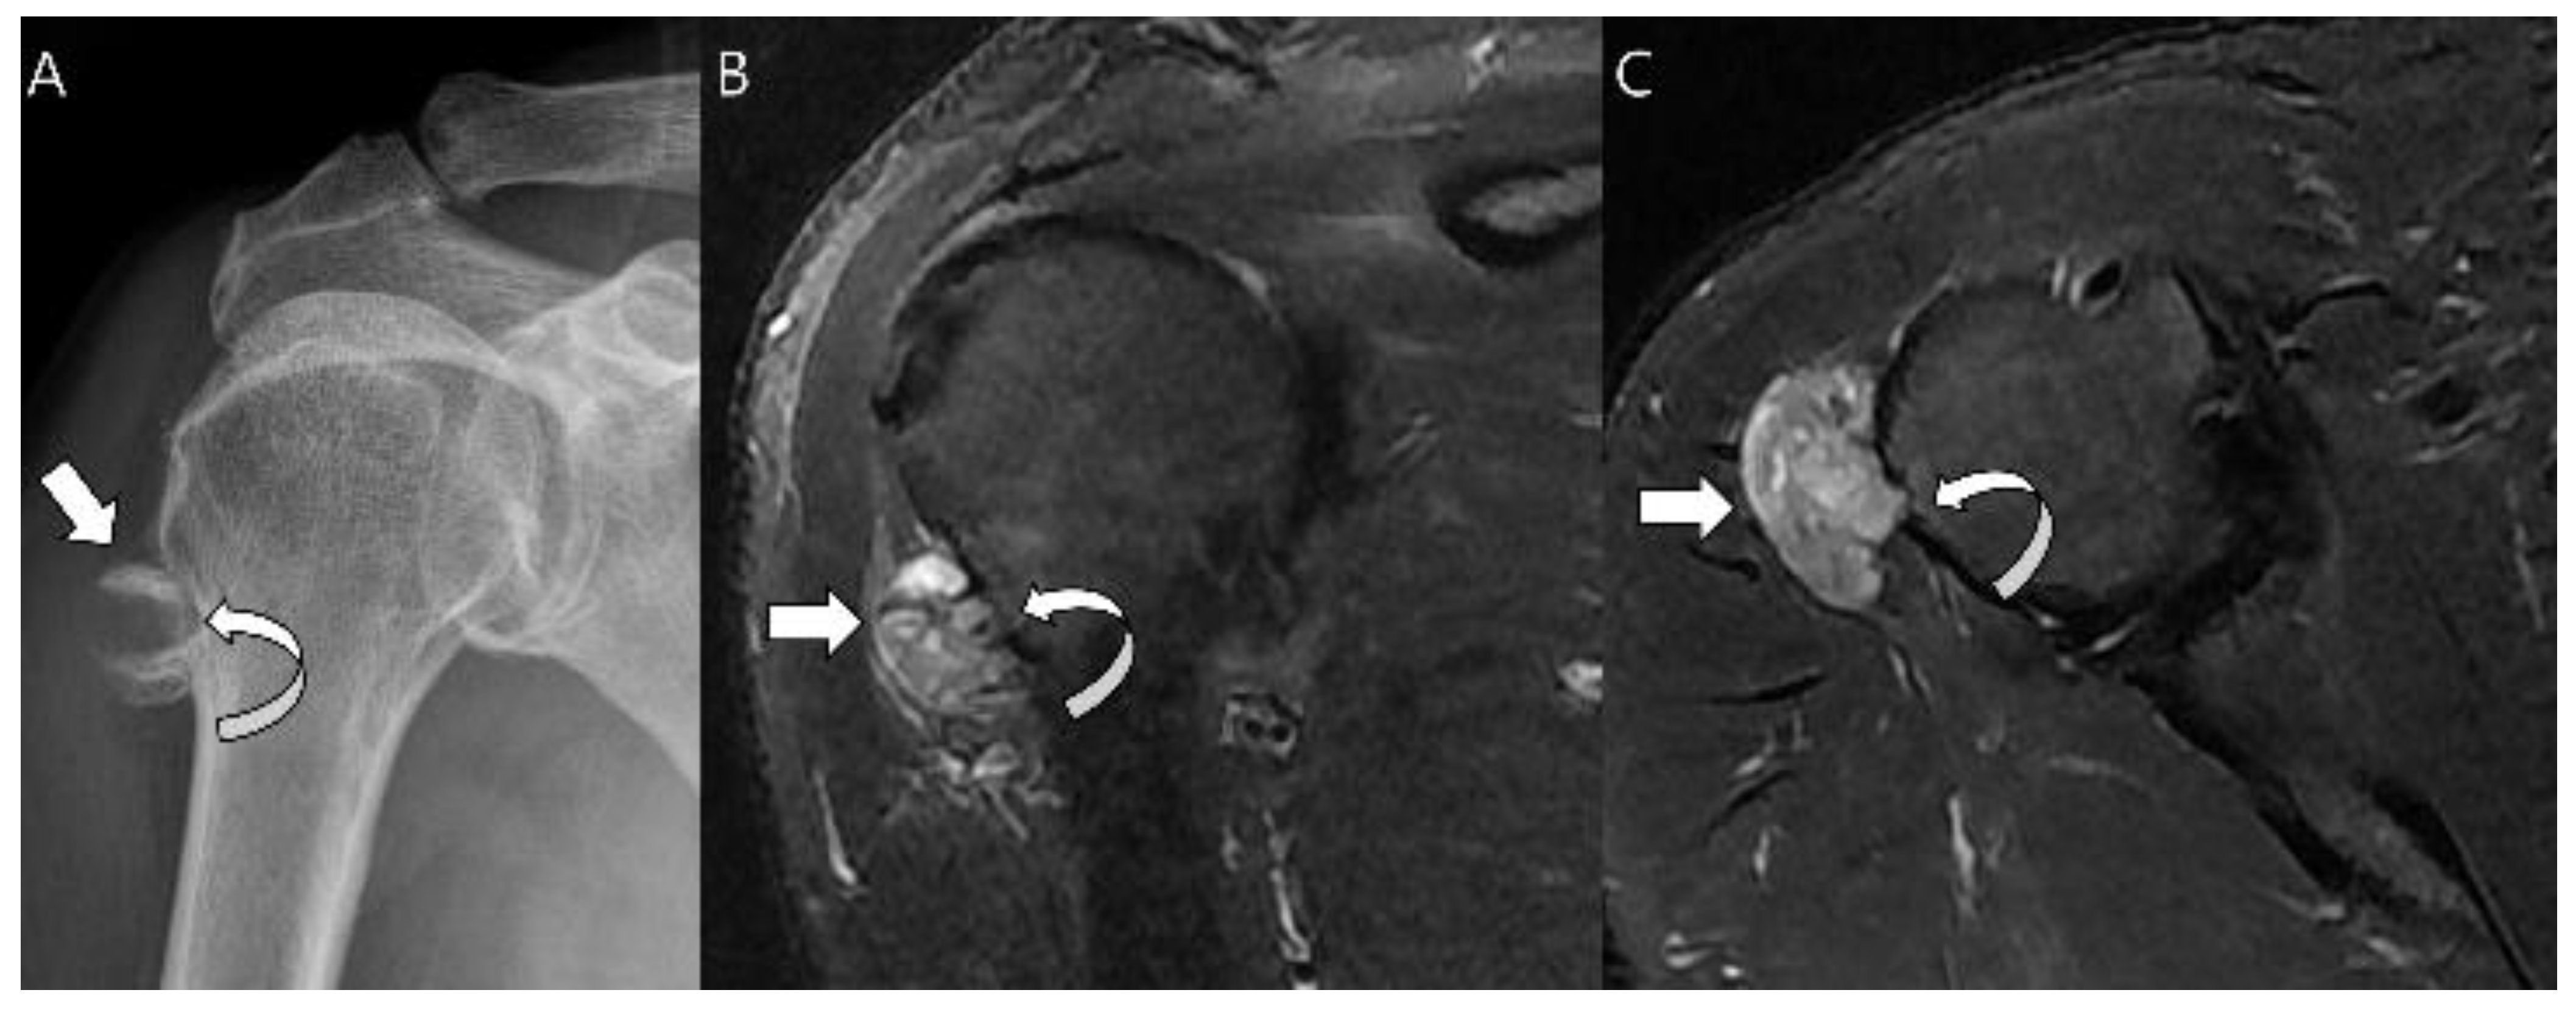

Radiographs show a round to oval lobulated soft tissue mass on the surface of the bone, lifting the periosteum over the tumor as a fibrous pseudocapsule [1,5]. The underlying cortex is almost invariable, presenting as either thickened or thinned, while complete cortical destruction is rare [5]. A Codman triangle may be seen where the periosteum is lifted [1]. Typical chondroid matrix mineralization is usually present and metaplastic ossification is often seen to a variable extent [1]. The medullary canal is typically not involved, although extension has been observed on MRI [1,40,41] (Figure 11). Periosteal chondroma and periosteal osteosarcoma are the most difficult tumors to differentiate from periosteal chondrosarcoma [43,44]. Tumor size is the only differentiating feature between periosteal chondroma (median size 2.5 cm) and periosteal chondrosarcoma (median size 4 cm) [40]. Periosteal osteosarcomas and chondrosarcomas both contain cartilage, but chondrosarcomas show no osteoid formation on histological examination [41,43].

Figure 11.

Periosteal chondrosarcoma grade 1 of the humerus in a 66-year-old man. (A) Radiograph shows a juxtacortical mass with Codman’s triangles (arrow) in the humerus. Note the associated cortical thinning (curved arrow). (B) Coronal and (C) axial T2-weighted images with fat suppression show a juxtacortical mass with high signal intensity and lobular margins (arrows). The mass has caused cortical erosion (curved arrow) but no evident marrow invasion.